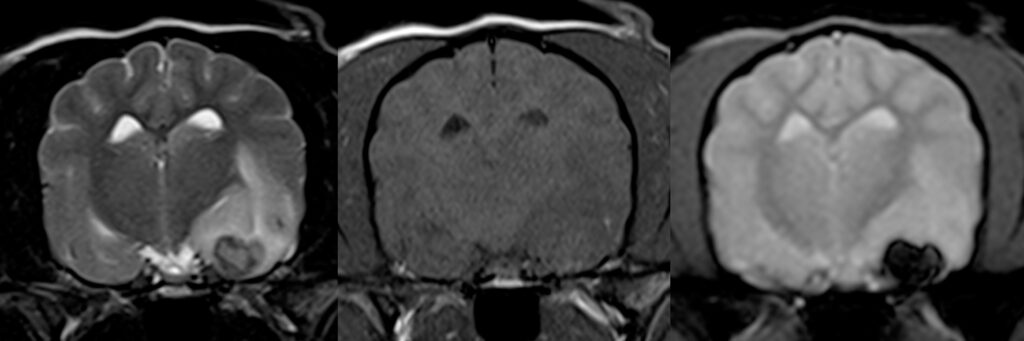

Figure 2. IRM d’un AVC hémorragique temporal gauche chez un chien Shetland.

De gauche à droite : séquence transverse T2, T1 et écho de gradient (GRE).

Noter l’aspect parfaitement hypointense (« noir ») de la lésion en GRE typique d’une lésion purement hémorragique.

Les AVC hémorragiques ont un comportement particulier bien visible en IRM en raison de la teneur et de l’évolution dans le temps de l’oxyhémoglobine contenue dans l’hématome. Les séquences en écho de gradient (T2*) exploitent cette caractéristique, les lésions hémorragiques étant particulièrement hypointenses dans cette séquence (Figure 2). La distinction des AVC hémorragiques de certaines tumeurs hémorragiques reste parfois délicate même si ces dernières ont plus souvent un contenu hétérogène voire une zone non hémorragique.